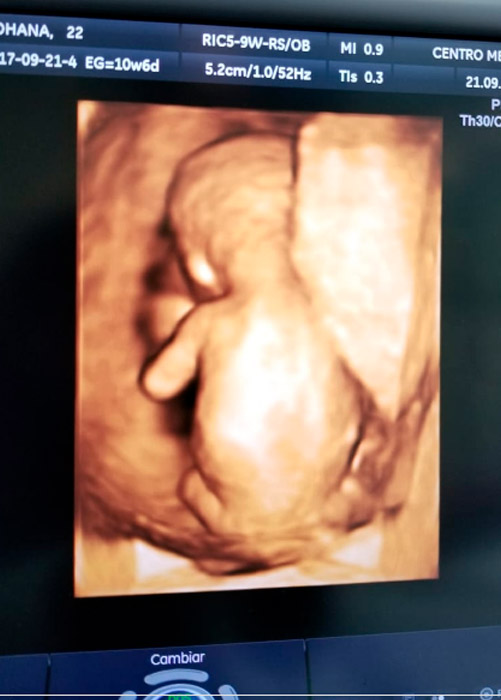

Primer Trimestre O Ecografía precoz: muy importante para confirmar embarazo, vitalidad embrionaria (si existe frecuencia cardiaca), determinar edad gestacional, ubicación o sitio de implantación y descartar embarazos ectópicos (no localizado en el lugar habitual en el útero sino en otro inadecuado), número de embriones, en caso de gestación múltiples, determinar cigocidad y corionicidad. Revisar si hay presencia desprendimiento de placenta o hematomas.